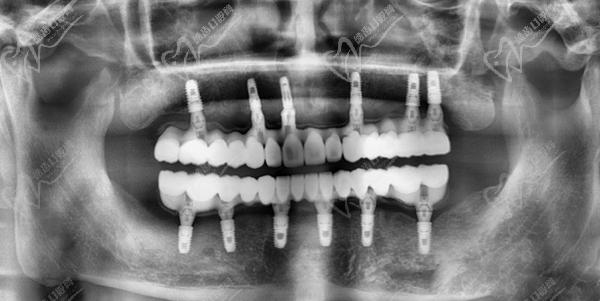

五、廣州鼎植口腔半口種植牙范例

患者張女士,53歲,上頜6顆牙缺失,咀嚼功能差。劉昭醫(yī)生通過all-on-4技術(shù),4顆種植體支持12顆固定修復(fù)牙,當(dāng)天種牙當(dāng)天戴牙。術(shù)后修復(fù)體穩(wěn)固,咬合舒適,改善咀嚼功能,提升生活品質(zhì)。

王先生,62歲,上下頜左右兩側(cè)臼齒缺失,佩戴活動義齒多年,飲食受限,假牙松動。劉昭醫(yī)生采用all-on-6技術(shù),精 準(zhǔn)植入12枚種植體,設(shè)計28顆修復(fù)體。術(shù)后當(dāng)天戴牙,咀嚼功能明顯改善。定期復(fù)診顯示,種植體周圍骨結(jié)合緊密,修復(fù)體穩(wěn)固如初,王先生對治療成效十分滿意。